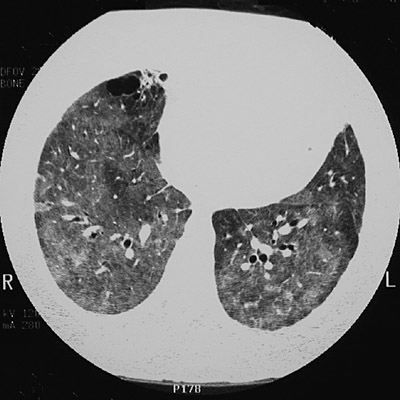

| This CT scan of the chest with the "lung window" setting reveals extensive irregular opacifications in all lung fields as a consequence of pulmonary alveolar proteinosis. The view in the upper lobes seen below demonstrates that the process is decreased toward the periphery. |